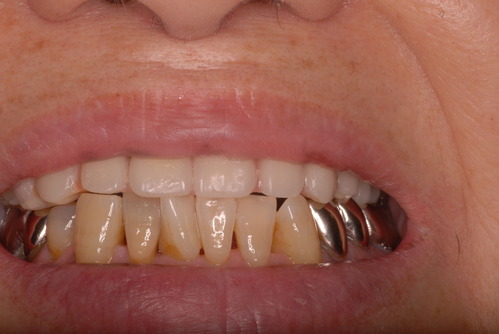

病気を治癒させずに矯正治療や破壊行為として神経を取り白い被せ物を入れた患者の末路です。

17才で上下矯正治療

22才で隙間が気になり、上京後、健康な歯の神経を取り削り見た目をよくする。

34才、奥歯や少し前の方の銀歯をセラミックなどの白いものに変更。

現在妊娠中で経過観察も中止。来院されたのはセラミックが取れたからでしたが、崩壊が激しく抜歯しかないような状態でした。それよりすべての歯は重症の歯周病に罹患していておそらく全ての歯は数年で抜け落ち、総義歯(総入れ歯)しかないと判断されたかたです。(そうはさせたくないのですが、本人は自覚していません。)

写真は殆ど崩壊し抜けたセラミックとその後修復してまだ経過監査中の歯の状態です。奥の歯は、重症の歯周病で注射もせずに抜いた歯です。